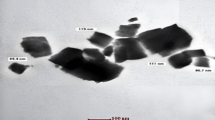

Surface morphology

The average diameter was 298 ± 4.45 nm and was determined by counting the more than 450 number of NPs visible in several SEM pictures, and by collecting SEM images of native LoR using the same dispersion and staining methodology as for the LoR dispersion. The NPs and NS have a tendency to aggregate or agglomerate, especially in aqueous solutions (diluted liquid). These aggregates can significantly affect the DLS measurements and result in variations in the PSD. The degree of aggregation leading to differences in the peak positions and intensities28. various instrumental factors, including laser intensity and detector sensitivity also responsible for these variations. DLS measurements involve statistical analysis of scattered light intensity fluctuations, and as such, inherent statistical variations can contribute to slight differences in the measured PSD values (Fig. 4a). The images revealed that the particles were spherical in shape, nanometric in size and was found to be porous in nature. It is most likely the result of DCM diffusing from the surface of the NPs during preparation because there are tiny pores on the NS's surface. Certain materials may exhibit surface reconstruction, faceting, or roughness, which can give rise to non-spherical features on the nanoparticle surface (Fig. 4b). To measure the average diameter of LoR-NS, which had previously been sonicated into a dispersion, SEM images were acquired29.